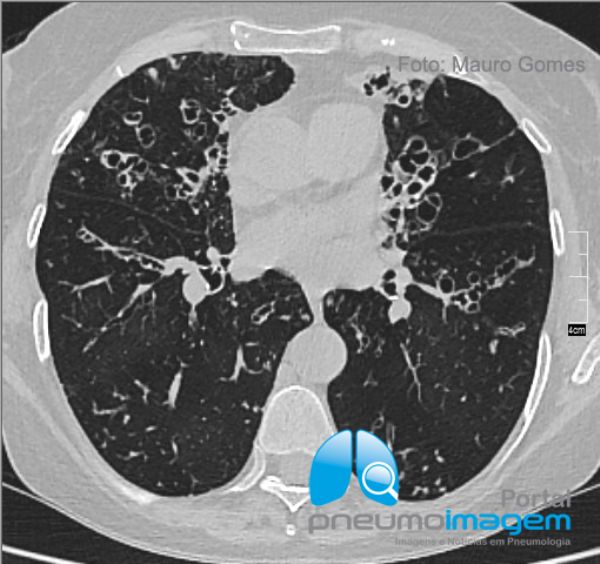

Bronquiectasias centrais nas regiões do lobo médio, lobo inferior direito, língula e lobo inferior esquerdo, além de nódulos centrolobulares difusos. As extensas bronquiectasias com impacção mucoide na língula determinam redução do volume desse segmento pulmonar.

Central bronchiectasis in the regions of the middle lobe, right lower lobe, lingula, and lower left lobe, in addition to diffuse centrolobular nodules. The extensive bronchiectasis with mucoid impaction in língula determine lung volume reduction of that segment.

Bronquiectasias centrais e nódulos centrolobulares difusos em ambos os pulmões. Essa é uma paciente do sexo feminino, 65 anos, asmática grave desde a infância e com exacerbações frequentes. Dosagem de IgE 1212 UI. IgE-RAST para Aspergillus fumigatus classe 4. Espirometria com distúrbio ventilatório obstrutivo grave (FEV1=0,87L/min - 36%). Na ocasião desse exame estava com infecção crônica por Pseudomonas aeruginosa mucóide.

Central bronchiectasis and diffuse centrilobular nodules in both lungs. Woman, 65, severe asthma since childhood and with frequent exacerbations. IgE 1212 IU. IgE-RAST for Aspergillus fumigatus class 4. Spirometry with severe obstructive ventilatory disorder (FEV1 = 0.87L / min - 36%). At the time of this examination was chronically infected with Pseudomonas aeruginosa mucoid.